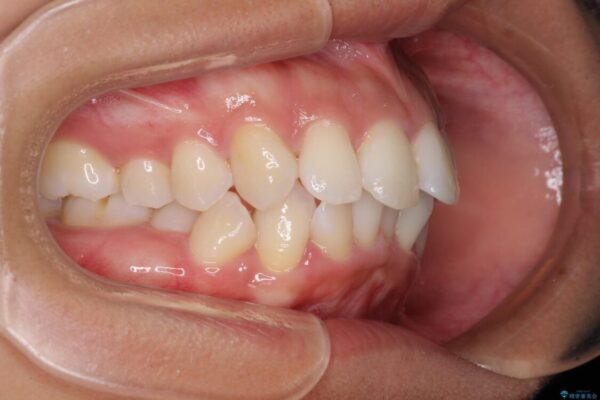

治療後

• 抜歯矯正で唇を閉じやすく 目立たないワイヤー装置 治療後画像